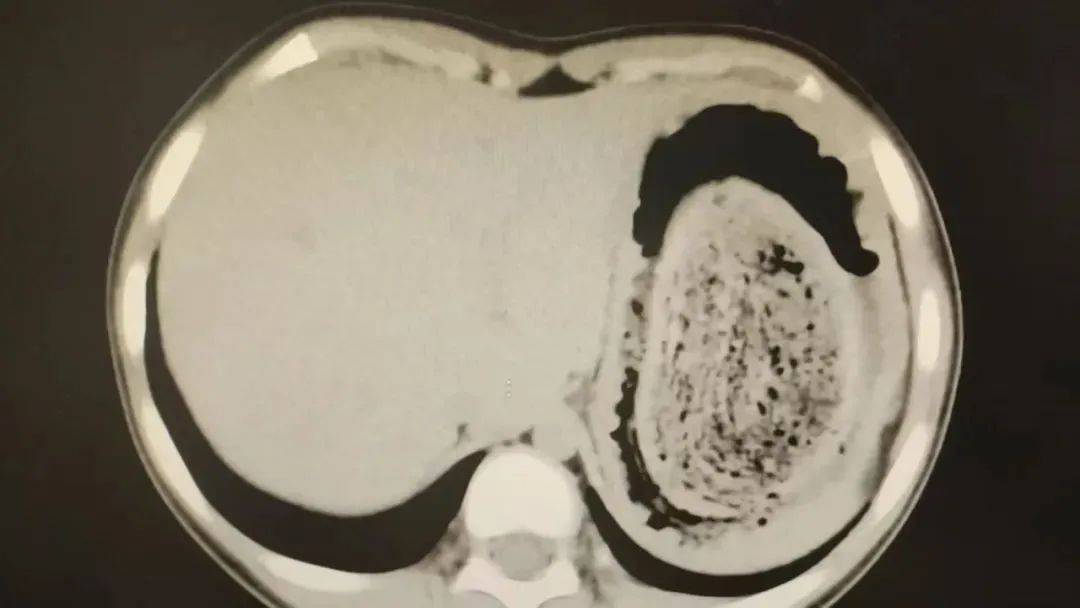

消化内科副主任医师陈琼发现,妮妮肤色惨白,甲床也是毫无血色皇冠信用网登2。血常规检查结果提示,孩子的血红蛋白仅59g/L,远低于正常值110g/L,属于重度贫血的状态,经过胃肠道超声检查,结果提示可能是“胃石症”。

在胃镜帮助下,妮妮胃里的情况逐渐明了皇冠信用网登2。一个滚圆黑色的毛发球混合着食物残渣占据整个胃腔,这些头发相互缠绕形成一个实心的“发石”,此外胃里还有一个鸡蛋大小的溃疡。

症结找到了,就是这个巨大的发石导致妮妮出现营养不良、贫血和闭经,当务之急就是取出“发石”,给胃进行“大扫除”皇冠信用网登2。

10岁女孩园园(化名)因持续3天的上腹痛伴呕吐被紧急送医皇冠信用网登2。影像学检查结果显示,她的胃部存在一个巨大的团块状阴影,初步怀疑为异物堵塞。据家长回忆,园园从1年前开始就有偷偷吃头发的习惯,但家人并未重视,直到这次症状严重才意识到问题的严重性。